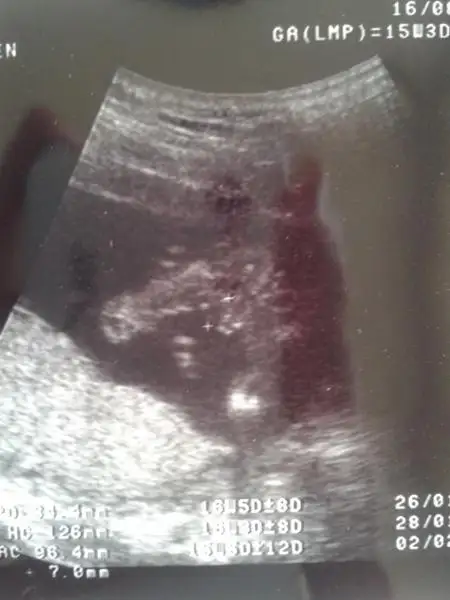

Face'de ekledim buraya da ekleyeyim dedim

Bakın teyzeleri oğluşumun nesi varmış burda

Eki Görüntüle 801171